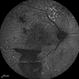

- Dengue Fever, rosacea conjunctivitis, preretinal hemorrhage

- Imaging device

- Fundus camera

- Fundus photograph of the left eye of a 32-year-old gentleman with dengue fever and thrombocytopenia. Photograph shows extensive retinal and pre-retinal haemorrhages, roth spots but no dengue retinitis. Same patient as in images 1-5.